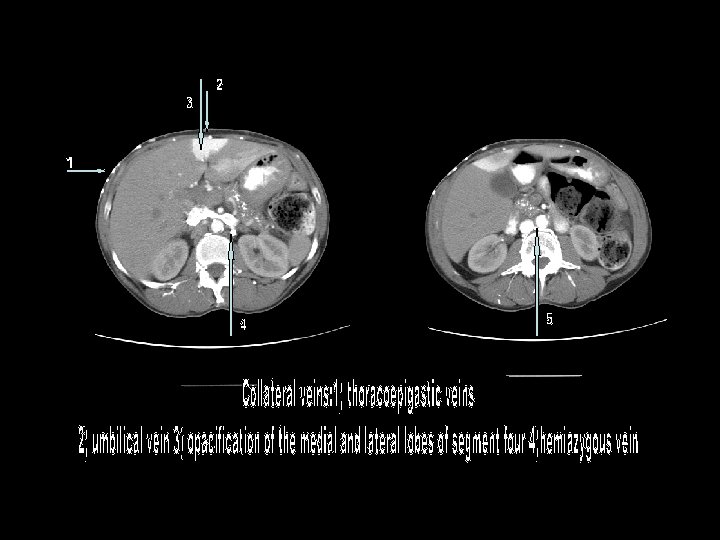

Venous Collaterals 1

Venous Collaterals Recruited to Bypass SVC and Azygous Veins 1 1

This case represents a Type 4 SVC obstruction, and demonstrates the collateral venous anatomy when the SVC is obstructed below the level of azygous insertion. With a patent azygous vein and the obstruction above the level of the azygous, collateral flow can travel retrograde into the left brachiocephalic vein to accessory hemiazygous vein to azygous vein and then flow antegrade through the distal SVC. With the Type 4 obstruction the collateral circulation is routed to the inferior vena cava or portal circulation by multiple venous plexuses, including: thoracoepigastric vein, mediastinal vein, internal mammary vein, hemiazygous vein, lateral thoracic vein, pericardiophrenic vein, paravertebral vein, intercostal vein, capsular /surface liver vein, bilateral phrenic veins, thoracodorsal scapular vein, superior/inferior epigastric vein, accessory hemiazygous vein. Another intriguing pathway illustrated in this example is the cavo-portal pathway associated with intense opacificaton of the quadrate lobe– a sign with high specificity for SVC obstruction. It is associated with communication of the internal mammary veins with the epigastric veins, which then anastomoses with the peri-umbilical venous channels. Through the recanalized umbilical vein in the falciform ligament, blood flows retrogradely into the left portal vein. The resultant flow and venous stasis is believed to result in the characteristic focal hepatic enhancement. Similar findings are observed nuclear imaging with Tc-99 m sulfur colloid scans, the so-call focal hepatic hot spot sign.